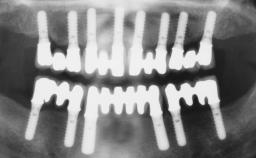

A 56-year-old female patient was referred to the clinic because of retention problems with her mandibular denture. She had been completely edentulous for more than 33 years and wore her sixth set of complete conventional dentures, which had been delivered 5 years previously. An oral surgeon had performed a vestibuloplasty in the interforaminal region of the mandible with a piece of skin tissue 12 years earlier. The panoramic radiograph and lateral cephalometric radiograph exhibited the hypotrophy of the inferior alveolar process. The mandible was a Cawood class VI,and the height of the mandible in the interforaminal zone was 15 mm.

Defining Characteristics Fully edentulous lower jaw to be rehabilitated with two or more implants

Modality 2 interforaminal implants

Bone Volume Horizontally and vertically sufficient

Loading Protocol Immediate (bar only)